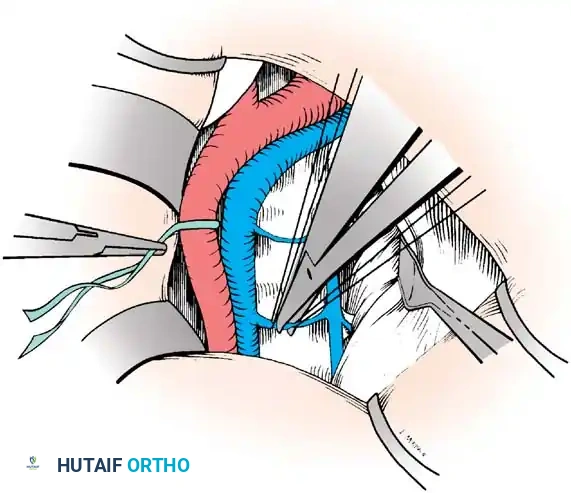

Vascular Management at the Bifurcation:

The approach to the L5-S1 disc space is dictated by the anatomic level of the aortic bifurcation.

* High Bifurcation: The safest approach is directly between the common iliac vessels. The primary vessels encountered here are the middle sacral artery and vein, which must be cauterized and divided.

* Low Bifurcation: The approach must be made lateral to the aorta, vena cava, and common iliac vessels. To safely mobilize the left common iliac vein to the right, you must meticulously isolate, ligate, and divide the iliolumbar and ascending lumbar veins. If a higher exposure is needed, ligate the 4th and 5th lumbar vessels.